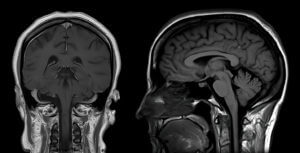

Magnetic resonance imaging (MRI) is a type of medical imaging technique that uses strong magnetic fields and radio waves to produce anatomical images. An MRI scan can be used to examine almost any part of your body, including your brain, spine, joints, heart, and blood vessels. MRI is of particular use in brain imaging. It